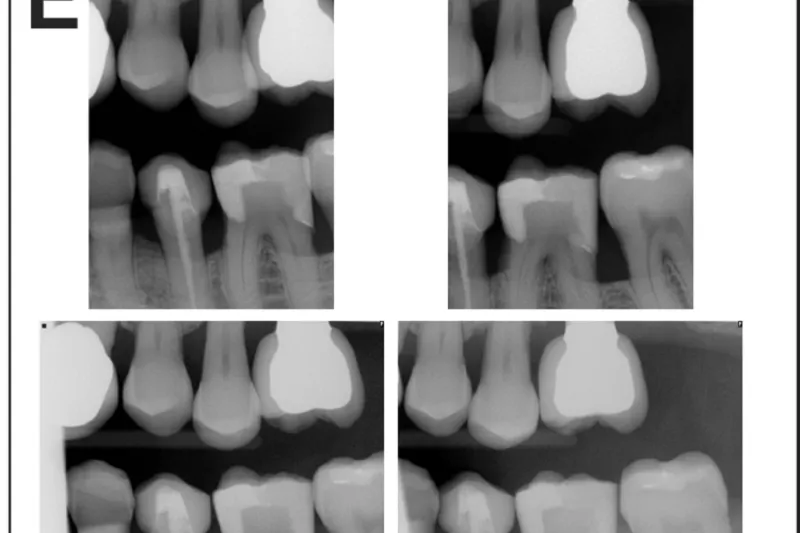

Formålet med undersøgelsen er at sammenligne den information, man får med to forskellige bitewingoptagelser, horisontale (HBW) og vertikale (VBW).

I røntgenjournaler fra Tufts University School of Dental Medicine (TUSDM) blev der søgt efter patienter, som havde knoglesvind omkring kindtænder og havde fået foretaget både HBW og VBW. I alt blev 320 journaler gennemgået efter seks kriterier: synlighed af marginal knogle fra hjørnetandens distalflade til den bageste tands distalflade, synlighed af horisontalt eller vertikalt knoglesvind, densitet af marginal knogle, synlighed af approksimale kontaktområder, synlighed af hele den anatomiske krone samt synlighed af furkaturer.

Der var signifikant flere VBW end HBW (P < 0,0001), der viste tab af det marginale knogleniveau (52,81 % vs. 3,75 %), typen af knoglesvind (vertikalt eller horisontalt) (50,94 % vs. 3,75 %), knogledensitet (28,75 % vs. 0,63 %), kontaktområder (20,63 % vs. 14,38 %) og furkaturer (43,44 % vs. 1,25 %). Der var flere HBW end VBW, der viste hele den anatomiske krone. Der var ingen signifikant forskel på antallet af optagelser pr. sæt HBW og VBW.

For patienter med marginal knoglesvind er VBW bedre end HBW, når det drejer sig om vurdering af den marginale knogles niveau, densitet og morfologi samt furkaturområder og vurdering af approksimale kontaktområder med henblik på cariesdiagnostik. Vi anbefaler uddannelsessteder for tandlæger, tandplejere og klinikassistenter at undervise i vertikal bitewingteknik som en standardmetode ved røntgenundersøgelse af voksne patienter med tegn på interdentalt knoglesvind i kindtandsområder.

Tandlæger bruger rutinemæssigt bitewingoptagelser (BW) for at følge caries, restaureringer og alveolære knogleforandringer. Uheldigvis udviser horisontalt placerede BW-film begrænset gengivelse af tænder og knogle. Vor sammenligning af BW fra de samme patienter undersøgte, om vertikal placering af BW- filmene kunne kompensere for disse diagnostiske begrænsninger. De vertikale BW-optagelser var klart bedre til diagnosticering af den marginale alveolære knogle, furkaturer og parodontale knogledefekter samt visualisering af de interdentale kontakter. Derfor kan det anbefales at anvende vertikale BW i stedet for horisontale BW-optagelser til alle patienter med parodontale forandringer og til mange patienter i øvrigt.